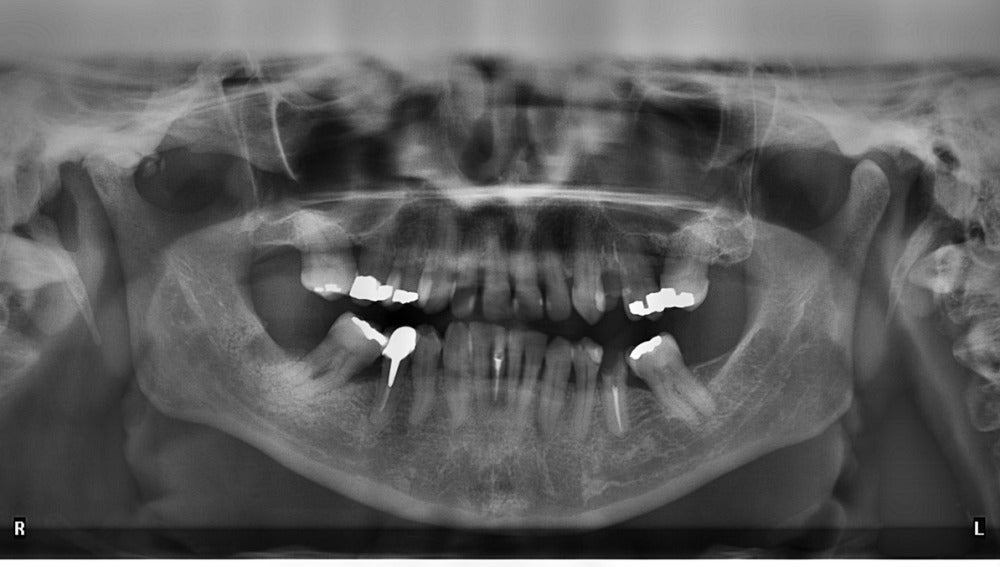

Todos conocemos lo que son los empastes y hemos tenido que acudir al dentista por ello. El proceso de limpiar la cavidad resultante de una caries y luego rellenarla con algún material, impide que vuelva a producirse la lesión cariosa pero no dura para siempre.

¿Es posible un empaste que nos dure siempre? Un equipo de científicos británicos ha desarrollado un tipo de empaste que dura toda la vida. El compuesto, no solo bloquea que se formen cavidades sino también evita el daño de las bacterias, ya que  libera minerales tales como calcio y fosfato, que el diente utiliza para formar nuevos minerales y repararse a sí mismo. Todo un hito en odontología.

El novedoso relleno está hecho de materiales compuestos de vidrio bioactivo que liberan fluoruro, así como de calcio y fosfato necesario para formar el mineral del diente. Los huecos se rellenan con minerales, evitando que las bacterias entren en los agujeros minúsculos entre el relleno y el diente y que pueden conducir a más cavidades y, por tanto, a la caries secundaria.

Lo que vemos de los dientes, su parte más superficial, es el esmalte, un tejido duro; sin duda, el mas duro y mineralizado de nuestro organismo. Es una estructura mineral compuesta en un 96% de materia inorgánica y un 4% de agua, y su papel es el de ser un escudo protector ante las bacterias -sobre las estructuras internas del diente- y que permita a su vez la masticación. Es una estructura inorgánica, por eso el esmalte no puede doler. Lo que nos duele es la dentina, que es una estructura mixta formada por una parte inorgánica (mineral) y por otra orgánica (prolongaciones nerviosas).

Se trata de una revolución en el cuidado dental y, por ahora, en las pruebas de laboratorio se ha demostrado que la auto-reparación de los dientes es efectiva. Teniendo en cuenta que los dientes son la única parte del cuerpo humano que no se regeneran por sí mismos, este avance resulta fundamental para la salud dental.